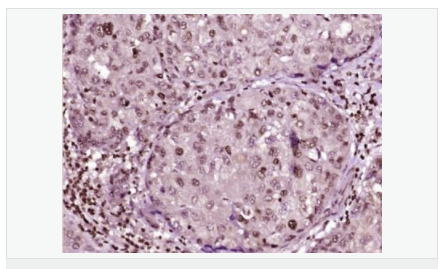

image.png